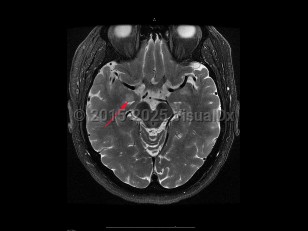

To distinguish encephalitis from other causes of encephalopathy, core components of the presentation of encephalitis include the presence of fever (within 72 hours before or after presentation), cerebrospinal fluid (CSF) pleocytosis (≥ 5 /mm3), or MRI or electroencephalogram (EEG) changes consistent with encephalitis.

Encephalitis is often secondary to a virus but may be caused by bacteria, fungi, or toxins. Three of the most common etiologic agents for acute encephalitis are viral including herpes simplex virus (HSV), varicella-zoster virus (VZV), and enterovirus. Alternatively, encephalitis can be caused by autoimmune conditions (anti-NMDAR encephalitis, lupus cerebritis) or inflammatory or paraneoplastic conditions, or be a consequence of stem cell transplant. Patients with encephalitis may also have concomitant meningitis (meningoencephalitis).